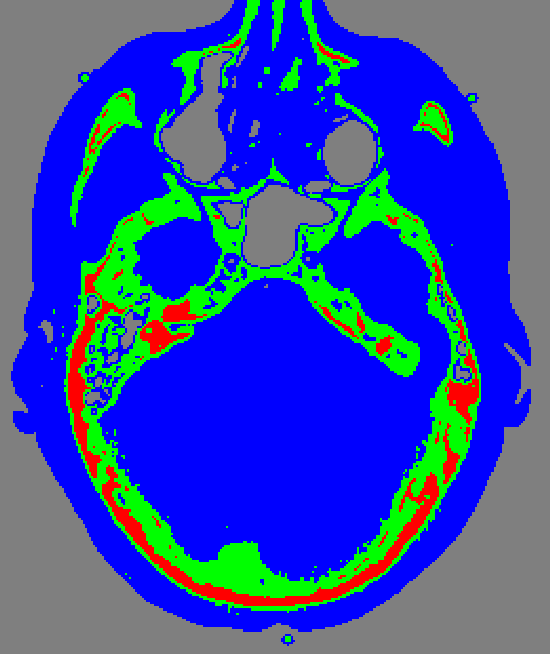

A CT scanning of the brain can reveal different anatomies and types of tissue. For example bone, trabecular bone, blood and brain tissue. Normally it is a trained radiologist that do manual recognition and analysis of brain images. In this course you will learn how a computer can be trained to recognise different tissue types. |